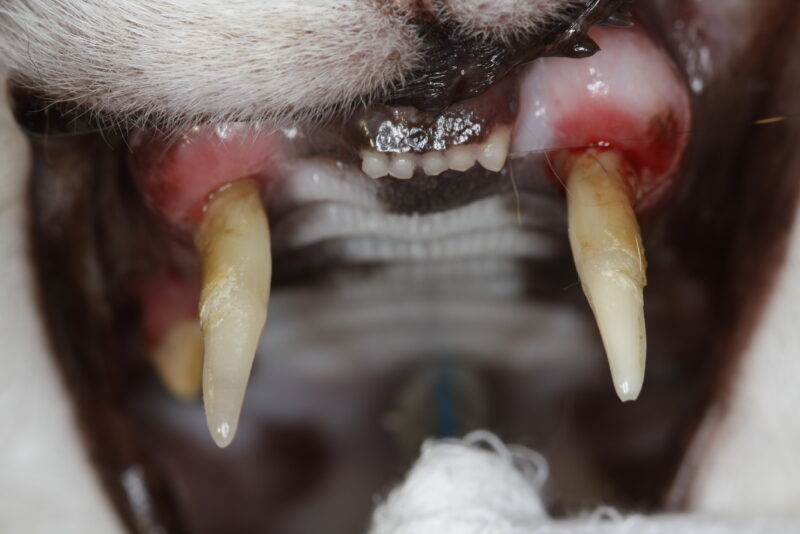

Die tägliche Erfahrung hilft uns dann, die richtigen Entscheidungen zu treffen. Zweifelsohne ist bei der Katze die komplette Dentalröntgenuntersuchung unverzichtbarer Teil einer fundierten Diagnosestellung geworden.

Ein Zahn mit einem grenzwertigen Befund wird beim geriatrischen Patienten möglicherweise eher gezogen als erhalten. Andererseits wird man sich beim älteren und beim Risikopatienten für eine möglichst unkomplizierte Vorgehensweise entscheiden. Sehr umfangreiche Operationen sollten im Interesse des Patienten möglicherweise auf mehrere Termine aufgeteilt werden. Somit ist ein besonderes Augenmerk auf ein gutes Zeitmanagement zu richten.